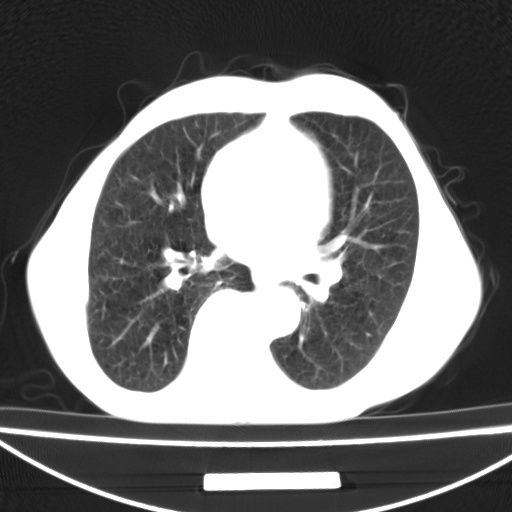

标题: CT13796:请会诊右上费病变!

患者男80岁,反复咳嗽多年,咳喘伴咯血1月

右上肺周围型肺癌伴肺门淋巴结转移.右上肺继发型肺结核.

右上肺周围型肺癌伴肺门淋巴结转移

右肺上叶占位性病变,考虑周围型肺癌,肺门淋巴结转移。要是能提供更多的临床资料就好了,以供鉴别诊断。

右肺尖周围型肺癌伴肺门淋巴结肿大

右肺尖结核

右肺上叶占位性病变,考虑周围型肺癌,肺门淋巴结转移。

右上肺周围型肺癌伴肺门、纵膈淋巴结转移

考虑为:右肺上叶肺癌伴阻塞性肺炎、右肺门及纵膈淋巴结转移。